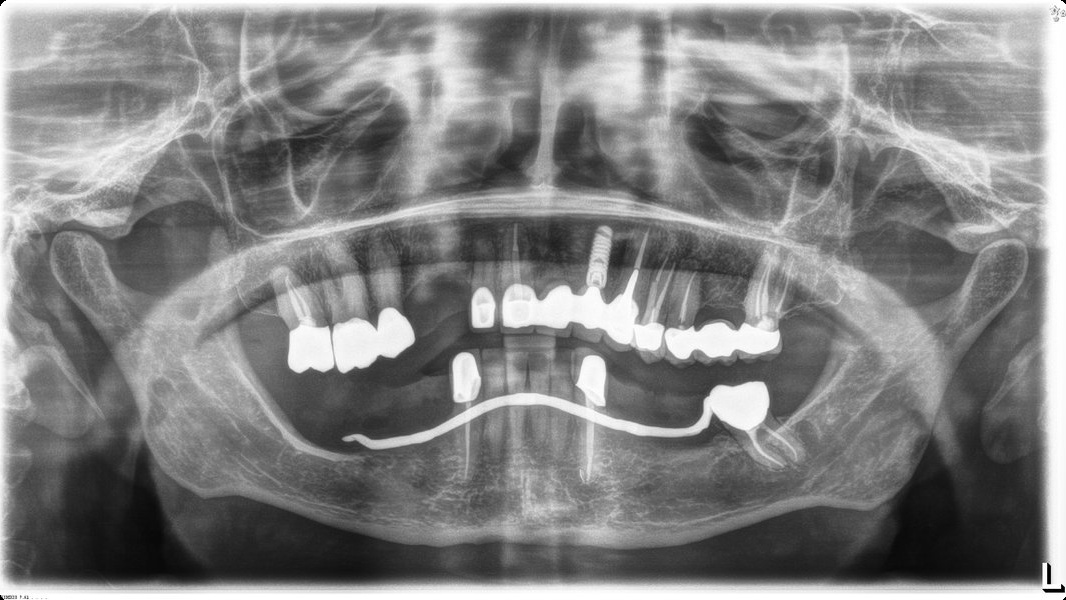

Micro-Vent 2

Connection Interface

Internal interface

Body Shape

Tapered body

Thread Design

ThreadedRounded threads

Straight flangeCurved apexRound hole